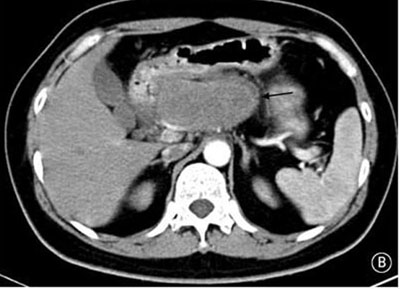

就診時(shí)實(shí)驗(yàn)室檢查結(jié)果顯示嚴(yán)重高血糖(血糖水平為982mg/dL[55mmol/L])。腹部CT檢查顯示胰頭部位出現(xiàn)一個(gè)9cm大小的腫塊(如圖B箭頭所示)??崭寡逡雀哐撬厮綖?30pg/ml(正常值≤80pg/ml)。